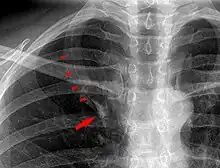

Azygos lobe on chest x-ray. Arrowheads show the delineation of the lobe. Arrow points to the azygos vein.

In human anatomy, an azygos lobe is a normal anatomical variation of the upper lobe of the right lung.[1] It is seen in 0.3% of the population.[2] Embryologically, it arises from an anomalous lateral course of the azygos vein,[3] in a pleural septum within the apical segment of the right upper lobe or in other words an azygos lobe is formed when the right posterior cardinal vein, one of the precursors of the azygos vein, fails to migrate over the apex of the lung and penetrates it instead, carrying along two pleural layers as the azygous fissure, that invaginates into the upper portion of the right upper lobe.[1]

An azygos lobe is usually an incidental finding on chest x-ray or CT scan. It is asymptomatic and not associated with any morbidity.[4][5] However, it can cause technical problems in thoracoscopic procedures.[6] The presence of the azygos lobe could alter the normal location of the superior vena cava or may be associated with other anomalies, including esophageal atresia or intrapulmonary right brachiocephalic veins.[7]